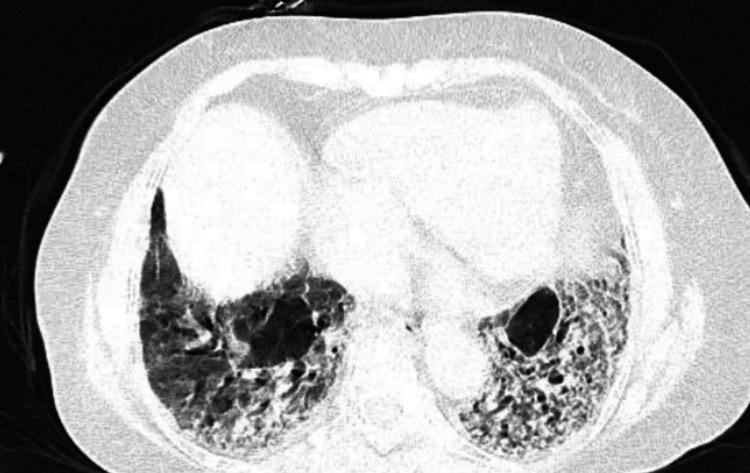

Juvenile systemic sclerosis (JSSc) is a rare autoimmune disorder that primarily affects children and adolescents. It is thought to be caused by a confluence of immunological, environmental, and genetic variables. The disease is characterized by excessive collagen production. It can result in symptoms such as shortness of breath, chest pain, difficulty swallowing, high blood pressure, and kidney problems. Although calcinosis cutis is common in systemic sclerosis, it is very rare in JSSc. We report the case of a 14-year-old female who presented with complaints of breathlessness for four days and multiple lesions in the sacral region for two months. She underwent surgical excision for calcinosis cutis in dependent regions. Early diagnosis and treatment of the condition are of immense importance in preventing mortality.

青少年系统性硬化症(JSSc)是一种罕见的自身免疫性疾病,主要影响儿童和青少年。它被认为是由免疫、环境和遗传因素共同作用引起的。该疾病的特征是胶原蛋白过度生成。它可导致呼吸急促、胸痛、吞咽困难、高血压和肾脏问题等症状。虽然皮肤钙质沉着在系统性硬化症中很常见,但在青少年系统性硬化症中非常罕见。我们报告了一例14岁女性病例,该患者主诉呼吸急促四天,骶部有多处皮损两个月。她接受了受压部位皮肤钙质沉着的手术切除。早期诊断和治疗该疾病对于预防死亡极为重要。